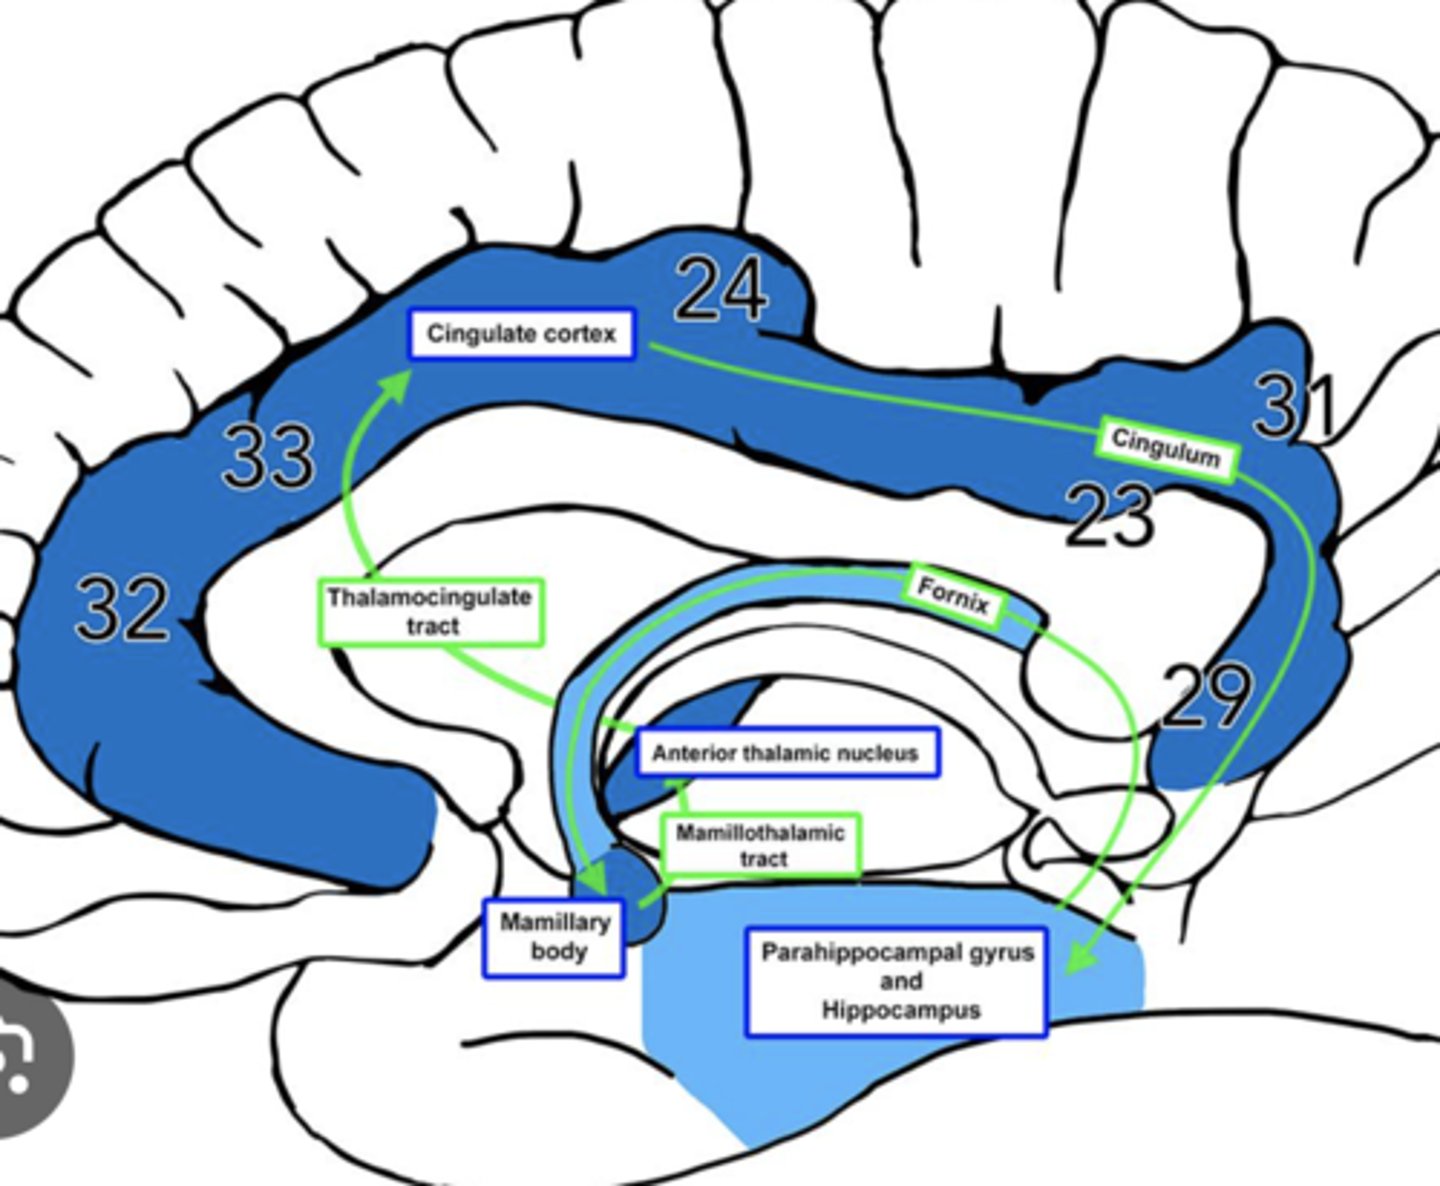

What is efferent to the anterior nuclei of the thalamus?

hippocampus via the cingulum

What is afferent to the anterior nuclei of the thalamus?

hippocampus and hypothalamus via mammillothalamic tract

What is the pathway from the hippocampus to the anterior nuclei of the thalamus?

1. hippocampus

2. fornix

3. mammillary nuclei

4. mammillothalamic tract

5. anterior nuclei (thalamus)

Where does the cingulate gyrus run?

superior to the corpus callosum